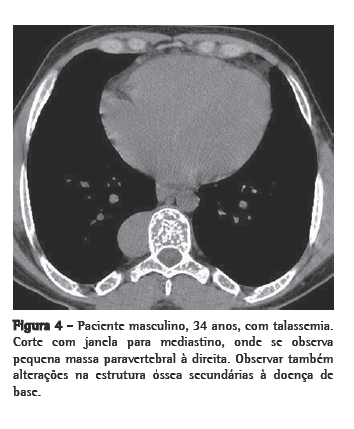

Como achados associados, dois pacientes mostravam calcificações no baço (Figura 4). Ambos eram portadores de anemia falciforme. Dos seis pacientes, dois haviam sido esplenectomizados, e em dois a imagem do baço era normal. Alterações ósseas relacionadas à doença de base foram identificadas em três pacientes.

Através da TC, podem ser observadas massas com densidade de partes moles, em sua maioria homogêneas, com características semelhantes às descritas na radiologia convencional,(1,2,5,6) que podem ou não ser realçadas após a administração do meio de contraste.(4,10) Este método de imagem é importante para analisar a estrutura interna das lesões, particularmente quando ricas em gordura,(5) para avaliar a presença de outras massas paracostais e para detectar alterações ósseas associadas a certas doenças hematológicas, como a talassemia e a anemia falciforme.(6) Nos casos relacionados a talassemia, anemia falciforme ou metaplasia mielóide, pode ocorrer um alargamento das cavidades medulares das costelas.(5)

O diagnóstico diferencial deve ser feito através das massas do mediastino posterior, incluindo tumores neurogênicos, linfoma, abscesso paravertebral, cistos extrapleurais, meningocele lateral, hiperplasia dos linfonodos mediastinais e neoplasias malignas primárias e metastáticas.(5,9)